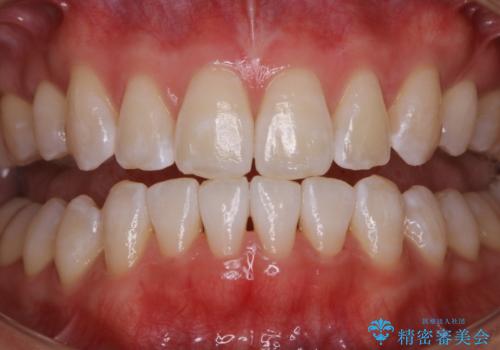

オフィスホワイトニング(エクセレントコース)

- オフィスホワイトニング希望で1日で白くしたいとのことでした。

オフィスホワイトニングのエクセレントコース(¥29700)を行いました。